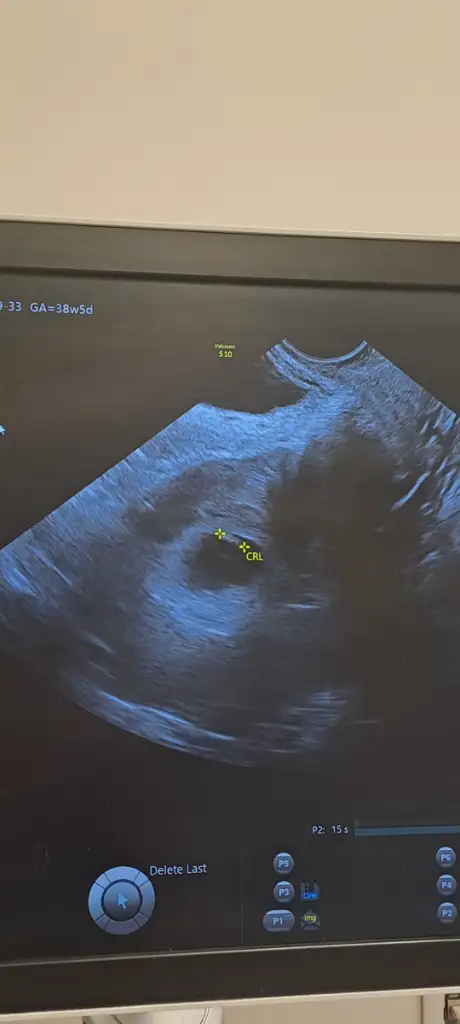

Y yagmur svn Üye Anneler Kulübü Kayıtlı Üye 11 Ocak 2023 52 0 16 36 19 Temmuz 2025 Konu Sahibi Konu Sahibi Takitoki #950 Merhaba 8+5 haftalık olduk cinsiyeti anliya bilen varmıdır